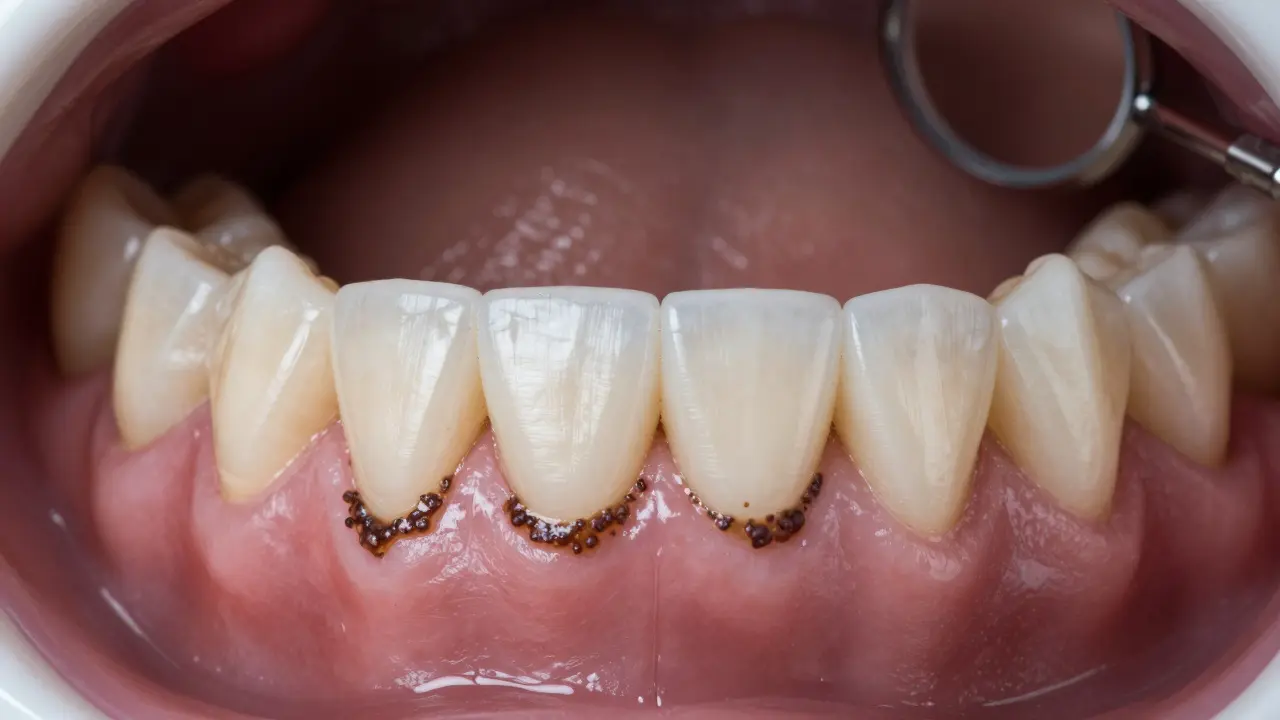

Zubní kámen není jen ošklivý - je to skutečný hrozba pro vaše zuby a dásně. Vzniká, když se plak, který se na zubech postupně hromadí, ztuhne pod vlivem minerálů ve slinách. Už po několika dnech se z něj stane tvrdá, tmavě žlutá nebo hnědá vrstva, kterou si neodstraníte běžným čištěním zubů. A pokud ho necháte, může vést k zánětům dásní, ztrátě zubů a dokonce k problémům s celkovým zdravím.

Mnoho lidí si myslí, že zubní kámen je jen nepříjemný vzhled. Ale to je velká chyba. Ten tvrdý nános je skutečným pěstí pro bakterie. Pod ním se rozmnožují škodlivé mikroby, které způsobují zánět dásní - gingivitidu. Pokud se to nezastaví, přechází do parodontitidy, kdy se rozpadá kost kolem zubů. Výsledek? Zuby se začnou hýbat, dásně se stahují a zuby mohou padnout. Studie z Journal of Clinical Periodontology ukazují, že lidé s neodstraněným zubním kamenem mají až třikrát vyšší riziko ztráty zubů ve srovnání s těmi, kteří pravidelně chodí na profesionální čištění.